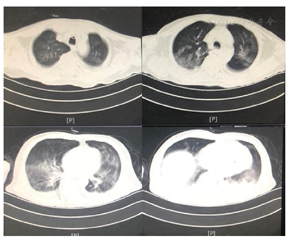

患者医学影像学检查如图1,图2,图3,图4,图5,图6,图7,图8所示,实验室检查结果如图9,图10,图11所示。

2021年3月24日患者出现顽固性低氧血症,血D2-二聚体:12810.00 ng/ml,CTPA显示肺动脉分支栓塞,双下肢静脉彩超:双下肢静脉血栓形成。加用抗凝治疗,调整康复治疗方案:(1)吸氧,监测血氧饱和度下完成康复训练项目;(2)依据患者耐受调整康复训练项目;(3)加强床旁呼吸功能训练。经上述治疗后,患者血氧饱和度有所上升,痰量有所下降,吸痰次数减少。结合患者肺部状况改善的情况给予佩戴说话瓣膜,约4 h/d,同时行语音训练,患者发音逐渐较前稍清晰,痰液可经口咳出,但仍有大量痰液瘀滞于咽部,需要辅助清除,血氧饱和度为85%~95%。2021年5月11日突发寒战、高热、皮肤花斑、咳嗽、大量咳痰,氧饱和度下降至60%。血象、感染相关指标升高;胸部CT:双肺炎症较前加重,双肺间质性病变;支气管三维重建:气管、支气管内分泌物,下叶各段支气管开口显示不清;痰培养:铜绿假单胞菌。经美罗培南抗感染治疗,并加强化痰、气管管理,加强翻身、拍背、排痰宣教后,患者未有发热,咳嗽、咳痰较前好转、感染指标正常;复查支气管三维重建:气道结构通畅;指脉氧饱和度:88%~97%。